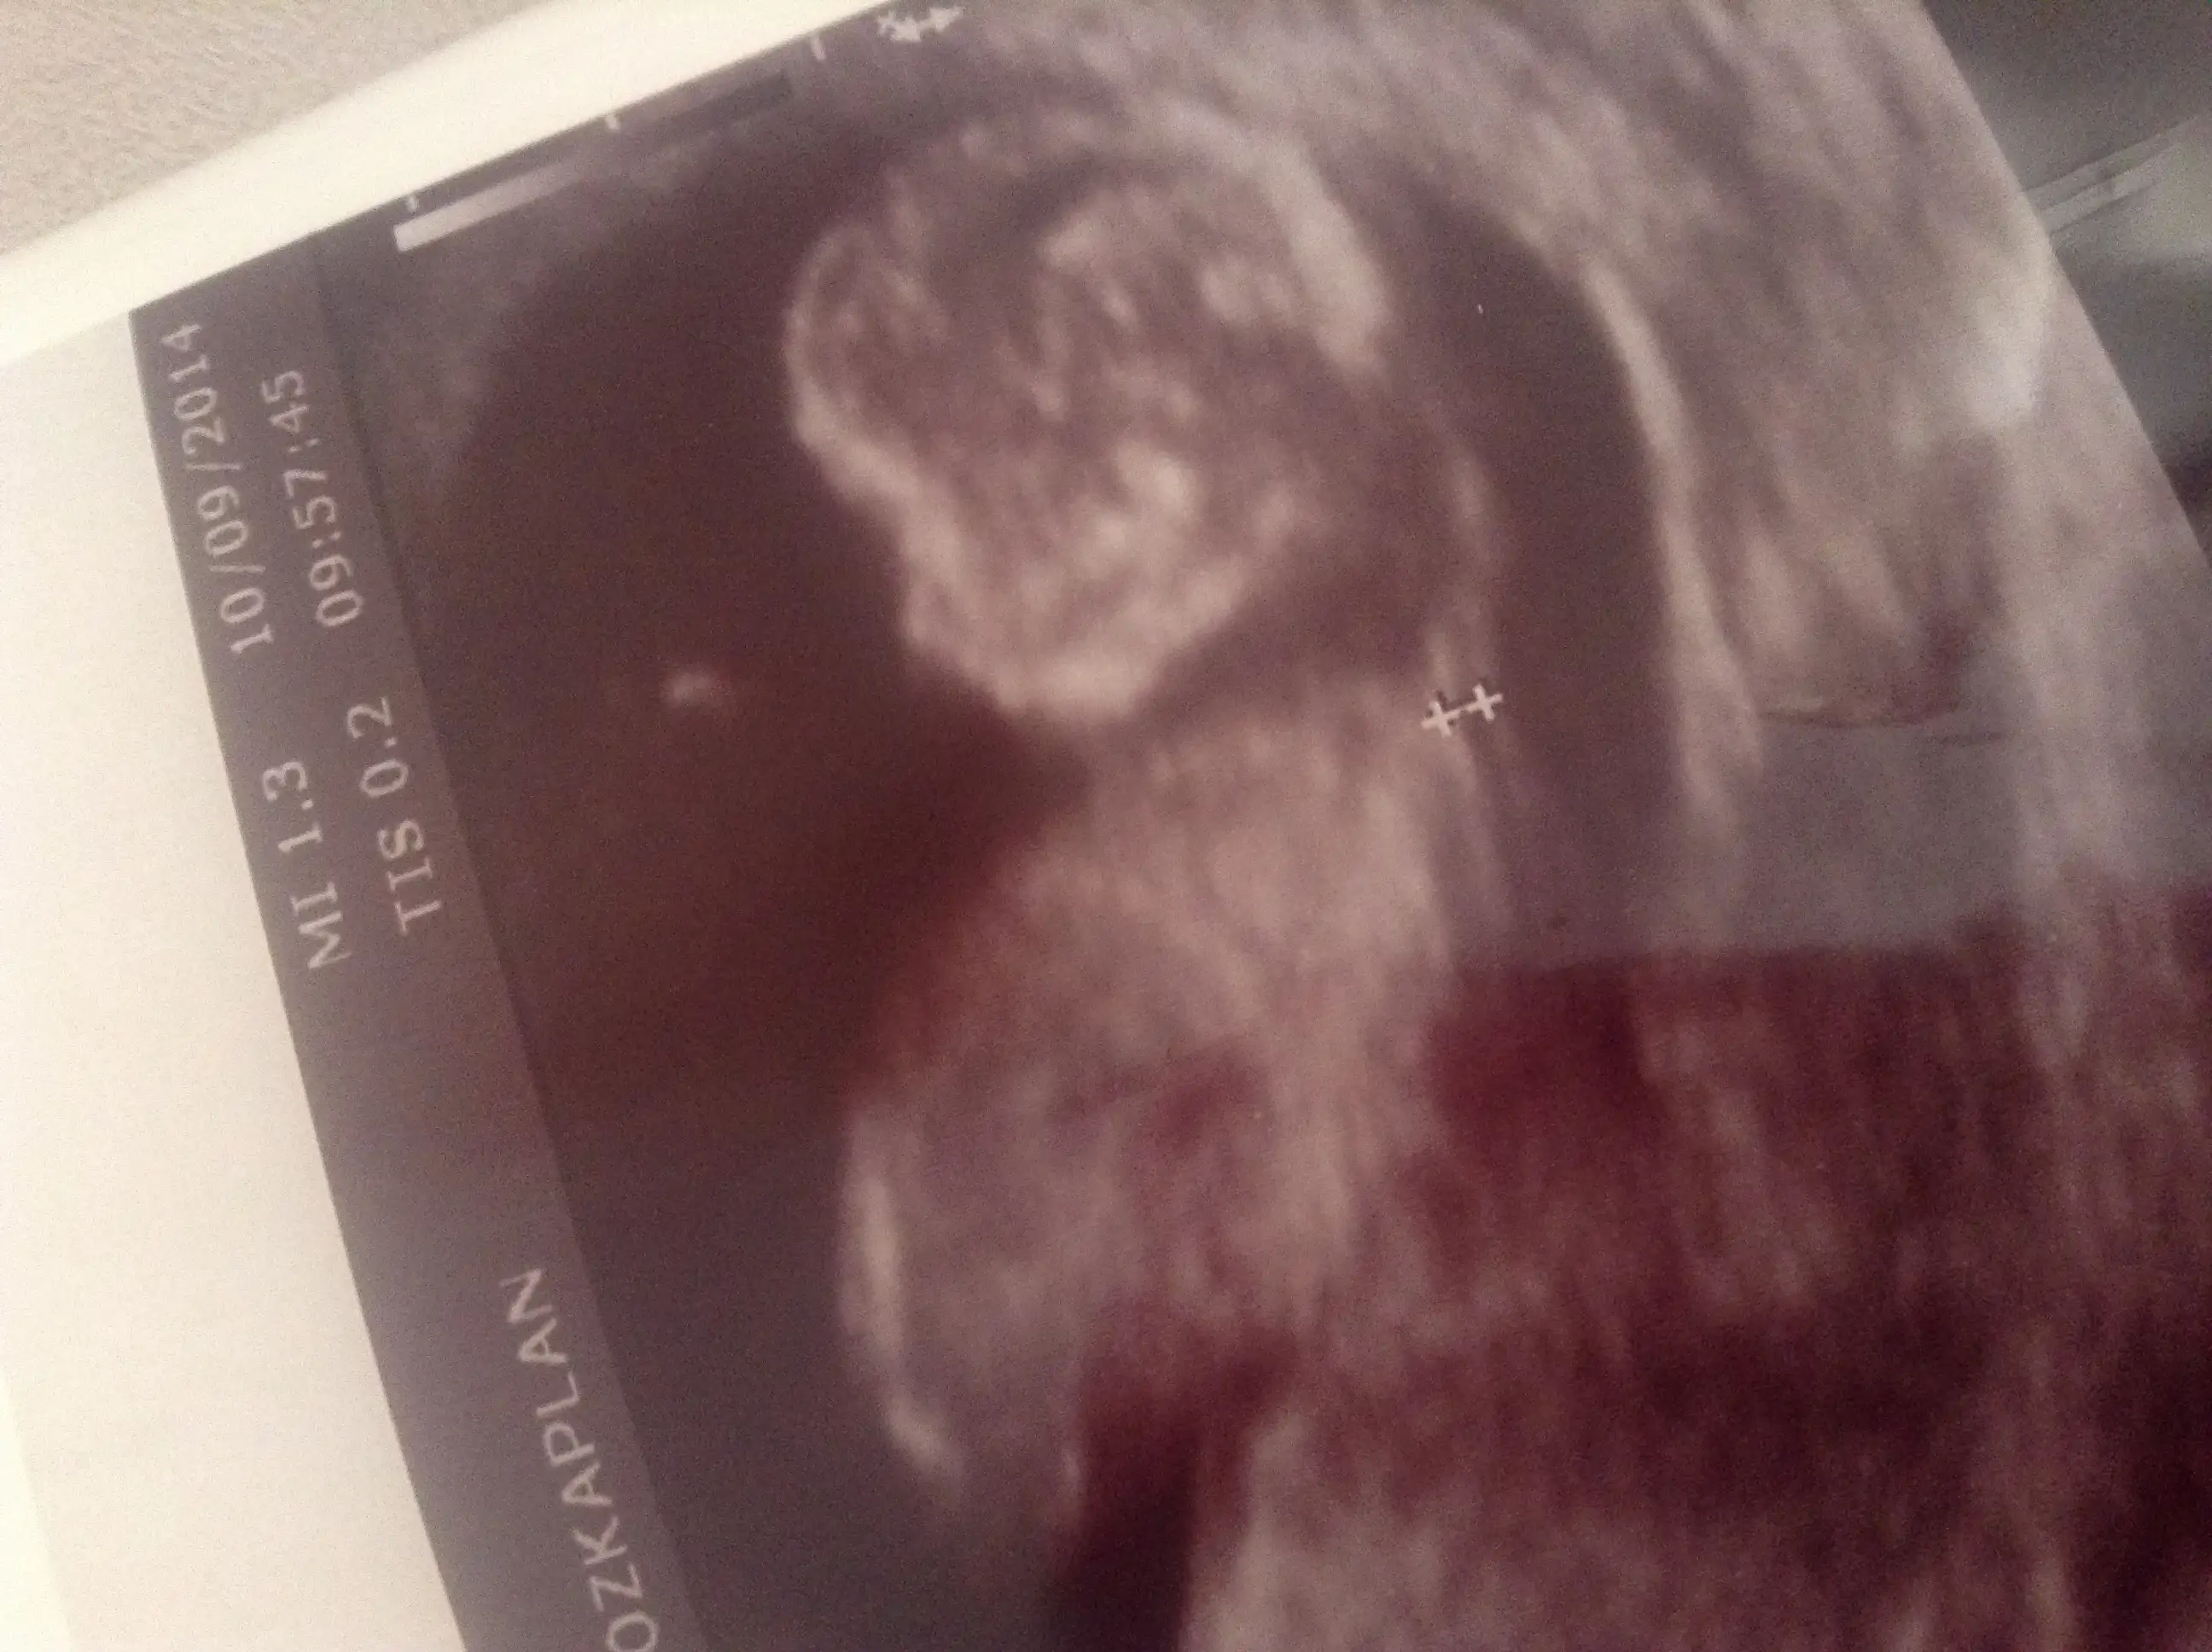

Bende 11. Haftadayım bebeğimin görüntüsü ektedir. Yorum yaparsanız sevinirim

Eklentiler

• image.webp

187,3 KB · Görüntüleme: 258